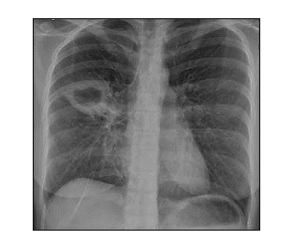

Homem, 40 anos, 60 kg, agente penitenciário, refere que há cerca de dois meses vem apresentando tosse seca, com episódios de febre ao fim do dia. Refere,também, emagrecimento não intencional e que tem se sentido cansado. Procurou atendimento médico diversas vezes, sendo prescrito antibióticos e “bombinha para asma”; porém, sem melhora. Nega tabagismo ou doenças. Atualmente, não está em uso de nenhuma medicação. Pesquisa de BAAR no escarro positiva. Realizada radiografia de tórax com o resultado a seguir:

Diante do quadro exposto, o tratamento adequado para este paciente é o esquema RHZE (150 + 75 + 400 + 275 mg) comprimidos/dia durante meses seguido por RH (300 + 150 mg) comprimidos/dia durante meses. Assinale a alternativa que completa correta e sequencialmente a afirmativa anterior.